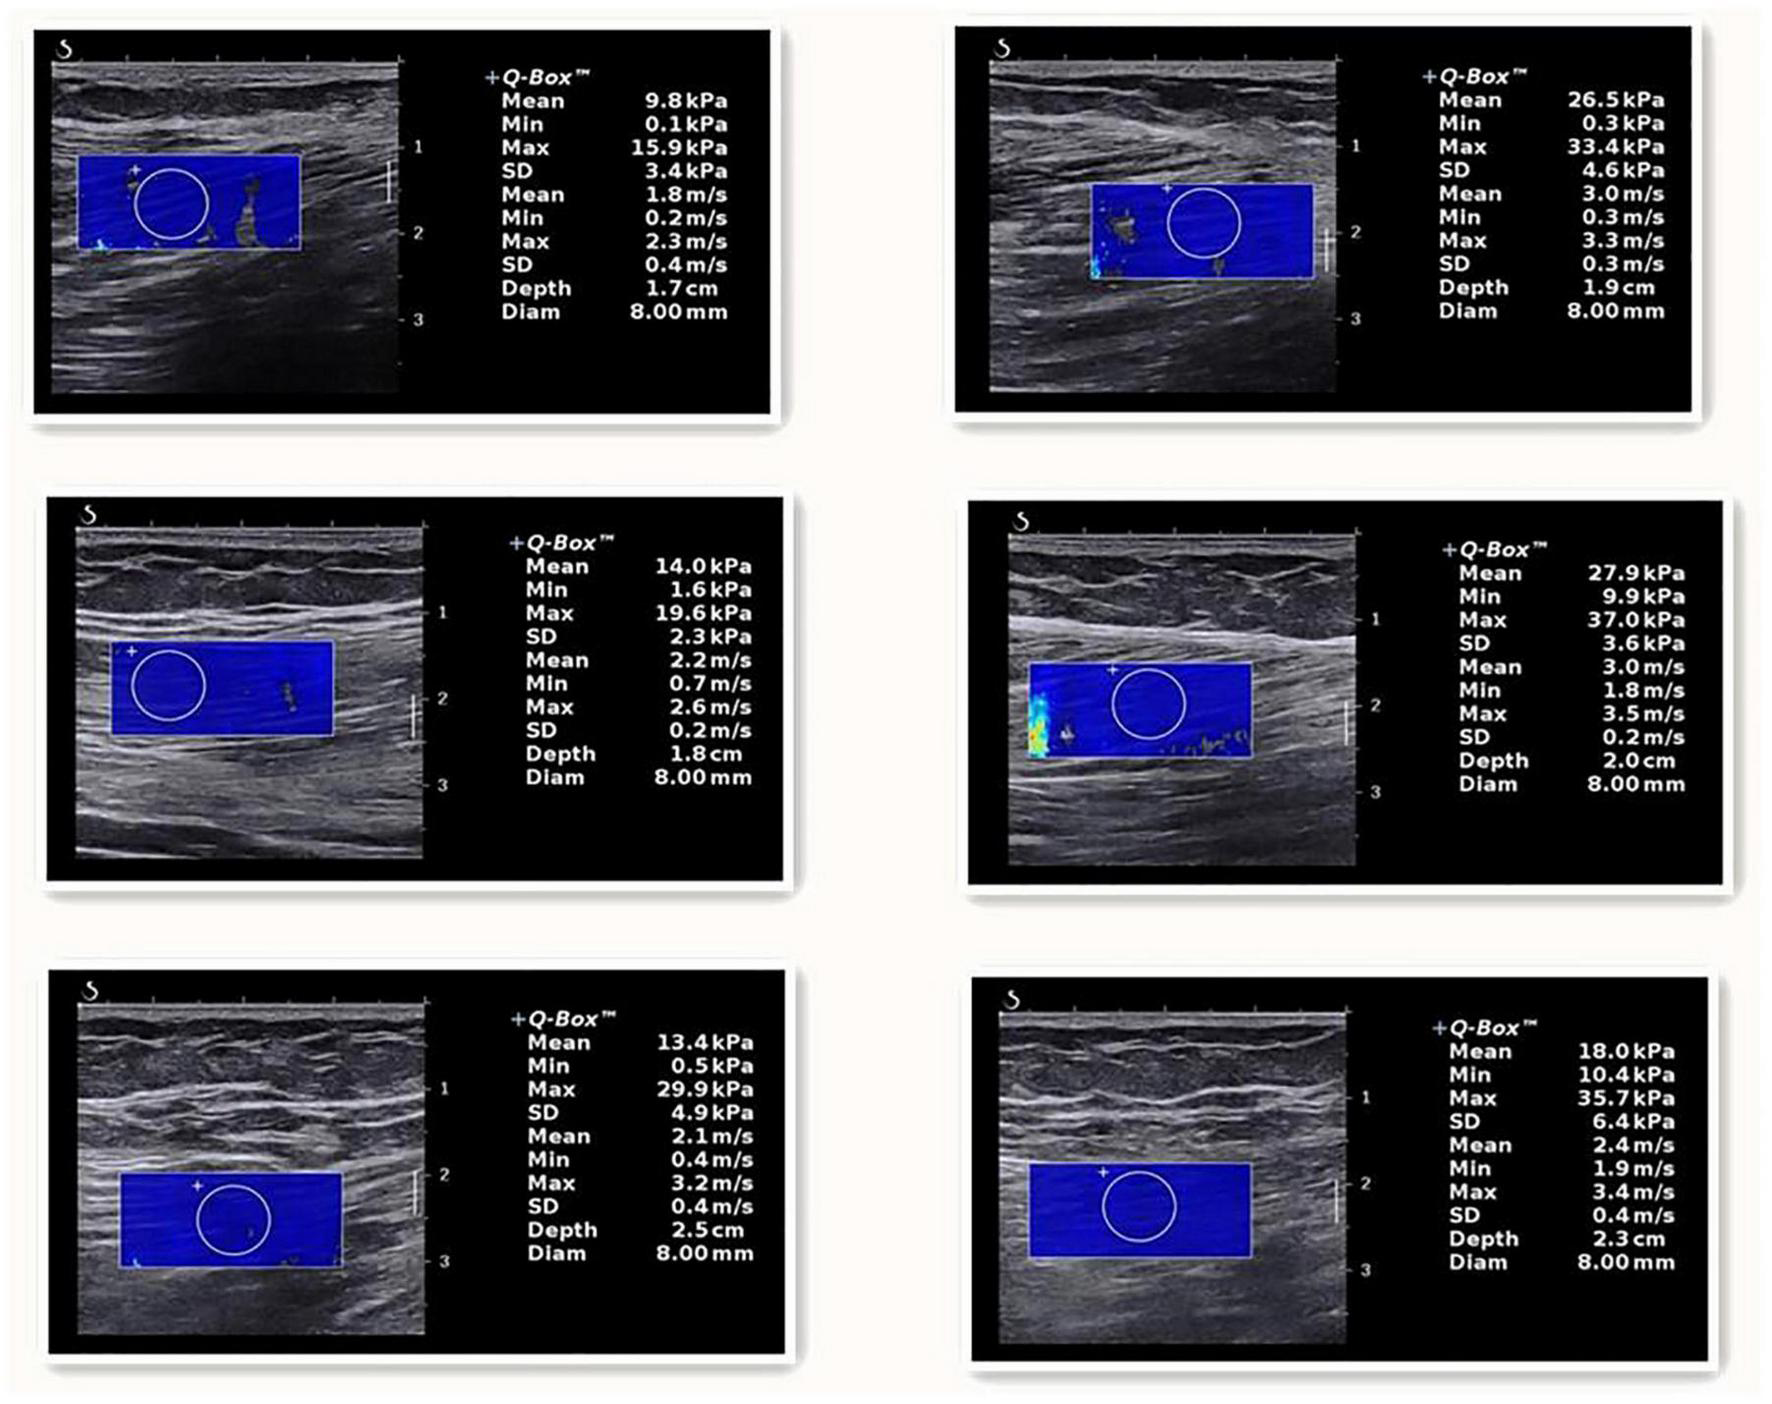

Our findings show that tissue shear modulus can be visualized in real time, while the difference between the sick and the healthy are readily observed and displayed via a color-coded map (Figure 1). These findings may shed more light on the mechanisms by which patients experience pain, stiffness, and limited functioning. This study demonstrated the feasibility of SWE techniques for assessing muscle stiffness in KOA patients. But the muscle assessed in this study was a superficial muscle that is easy to palpate. The same cannot be said for deeper muscles such as those in the lumbar region or deep abdominal area. Consequently, an inability to palpate and reproduce the classic referral patterns is difficult to accomplish for the clinician. Shear wave elastography would provide such a means for an objective evaluation of tissues of different types and depths, and a means to determine the efficacy and longevity of therapeutic interventions. Currently (Kwon et al., 2012; Berko et al., 2014), there are still no relevant reports on the normal young’s modulus of muscle tissue and the reference range of abnormal values, which will become the future research direction and play a greater role in the diagnosis of muscle injury, monitoring the development of diseases and evaluating the curative effect of diseases.

FIGURE 1

The one on the left is listed as a healthy person, and the SM, ST, and BFL are listed from top to bottom. The one on the right is a patient, and the SM, ST, and BFL are listed from top to bottom.